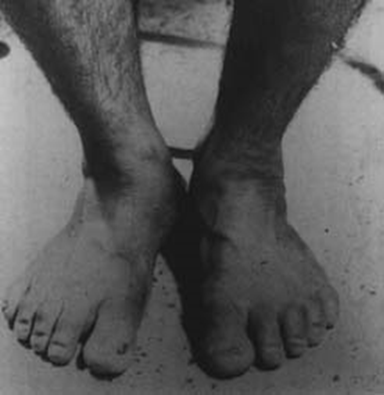

图三,这是一个在泰国男性头部的大型表皮疣状痣。他儿时说他记得他叔叔的生平,他叔叔被用大刀砍在头部砍死。(图片来源:childpastlives)

胎记和伤痕的一致纯属巧合的可能性在小孩有两个或更多胎记和去世的人伤痕一致时会显著减少。图三显示了一个泰国男性头部后面的主要皮肤异常(表皮疣状痣),他记得他叔叔的生平,他叔叔被用大刀砍在头部并立刻死亡。这个小孩还有一个在右大脚趾的变型的指甲,对应他叔叔在去世前多年受扰的同一脚趾的慢性感染。

图四,图四中泰国受访对象的先天右大脚趾甲畸形。这个畸形对应他叔叔(译者注:受访对象自认的前世)右大脚趾的慢性溃疡。(图片来源:childpastlives)